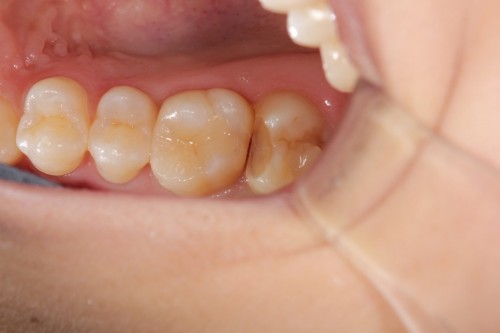

奥歯がしみるとの事でした。一見分かりませんが拡大鏡で確認して行くと虫歯が見つかりました。

虫歯を取った状態です。虫歯のみを取っています。